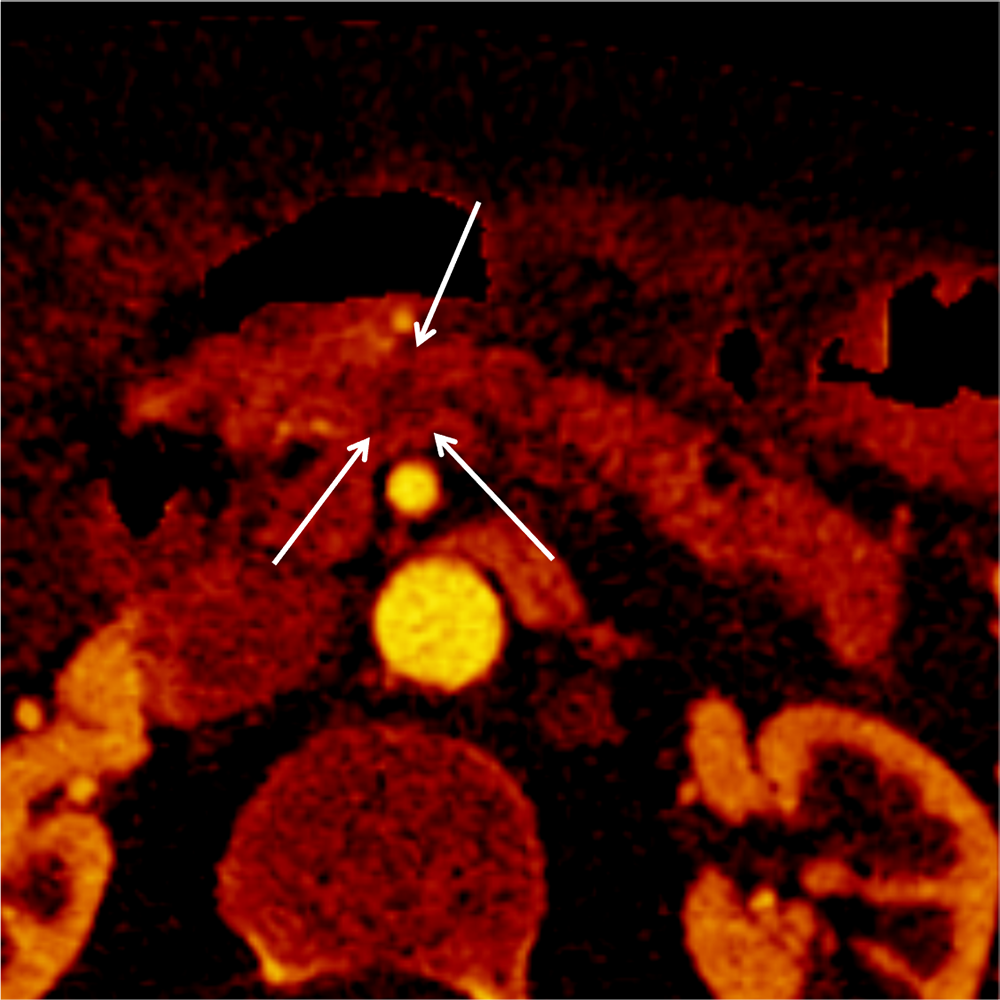

さらにthinスライスのCT画像、MPR(multi-planar reconstruction)、Dual-energy CTを用いた低エネルギーレベルの仮想単色X線画像やIodine mapの併用で、検出能向上や病期診断の精度向上につながると考えられる。Iodine mapは、Dual energy CTのデータからヨード造影剤を抽出して画像化したもので、ヨード濃度とその分布を把握することができる。本症例でも、Iodine mapでは病変と周囲膵実質のヨード濃度の差がわかりやすく、病変をより認識しやすくなった。また、MPR像を用いることで、通常の水平断面像と比べて、病変と主膵管との位置関係の把握が容易となった。